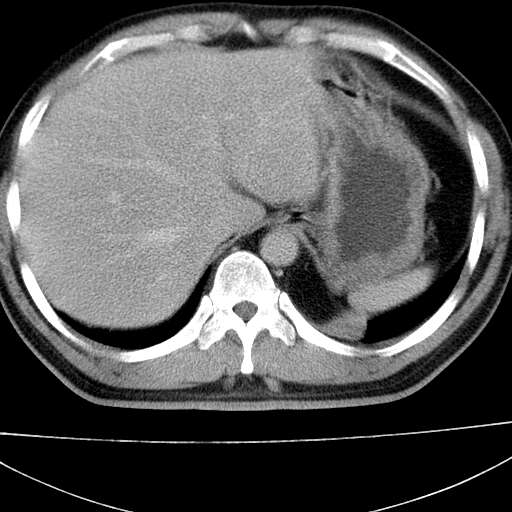

标题: CT21921:腹膜后腔肿物。患者男39Y。体检。增强扫描时间欠准

1)考虑左肺下叶后基底段(或左下胸后壁胸膜)软组织团块,性质待定;建议行进一步检查。2)左肾结石。

左膈肌连续性中断,左侧膈疝可能性大.

左下肺隔离症,可见从胸主动脉发出异常血管供应